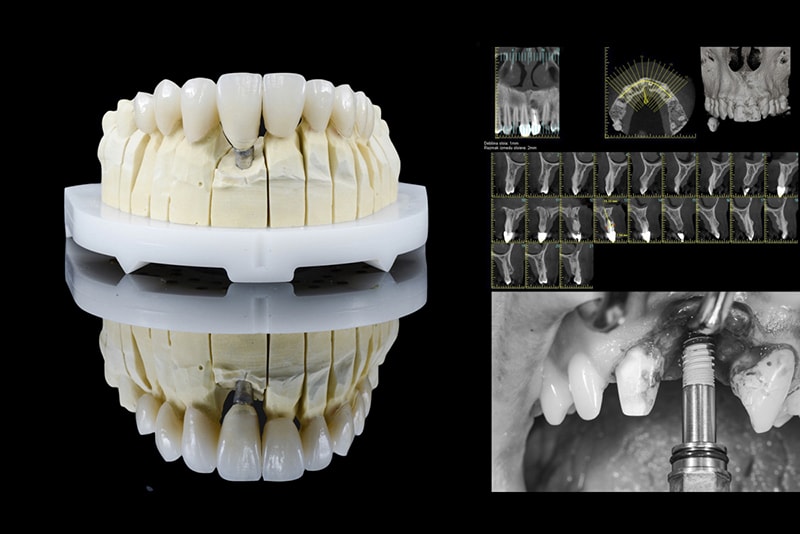

With Digital Smile Design we calculated exact measures for:

Treatment plan in chronological order:

• Extraction of fractured tooth and immediate dental implant loading with temporary crown

• Teeth whitening

• Full ceramic crown on implant with individual zircon oxide abutment

• Full ceramic crowns